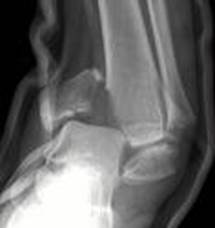

$$$010 https://images.google.ru/imgres? imgurl=https://ankleorif.com/db1/00096/ankleorif.com/_uimages/rivord2.JPG& imgrefurl=https://ankleorif.com/_wsn/page2.html& h=422& w=395& sz=17& hl=ru& start=24& um=1& usg=__D2aAwHaj7He8gr2Pw-id_NFDGdU=& tbnid=9Ys4VXNKat7VSM: & tbnh=126& tbnw=118& prev=/images%3Fq%3Dmalleolar%2Bfractures%26start%3D20%26ndsp%3D20%26um%3D1%26hl%3Dru%26lr%3D%26sa%3DNКак производится репозиция такого повреждения

A) Пронация и смещение стопы кнаружи

B) Супинация и смещение стопы кнутри

C) Сгибание и смещение стопы кзади

D) Разгибание и смещение стопы кпереди

E) Инверсия и ротация стопы кнутри

{Правильный ответ} = A